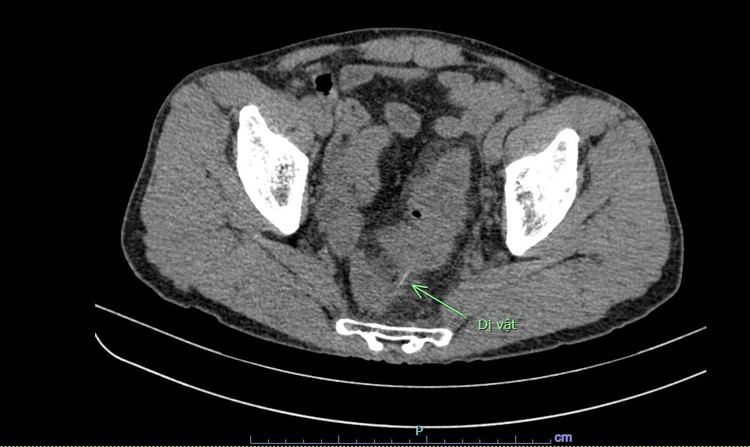

Hình ảnh chụp cắt lớp vi tính cho thấy dị vật đâm thủng đại tràng người bệnhHình ảnh chụp cắt lớp vi tính cho thấy dị vật đâm thủng đại tràng người bệnh

Trong quá trình phẫu thuật, bác sĩ kiểm tra thấy đoạn cuối đại tràng xích ma có 1 dị vật dài đâm thủng lòng đại tràng và chui ra ngoài. Lấy dị vật ra thì phát hiện đây là 1 chiếc tăm tre dài 10cm. Sau đó, các bác sĩ đã khâu lỗ thủng đại tràng và làm hậu môn nhân tạo cho người bệnh.